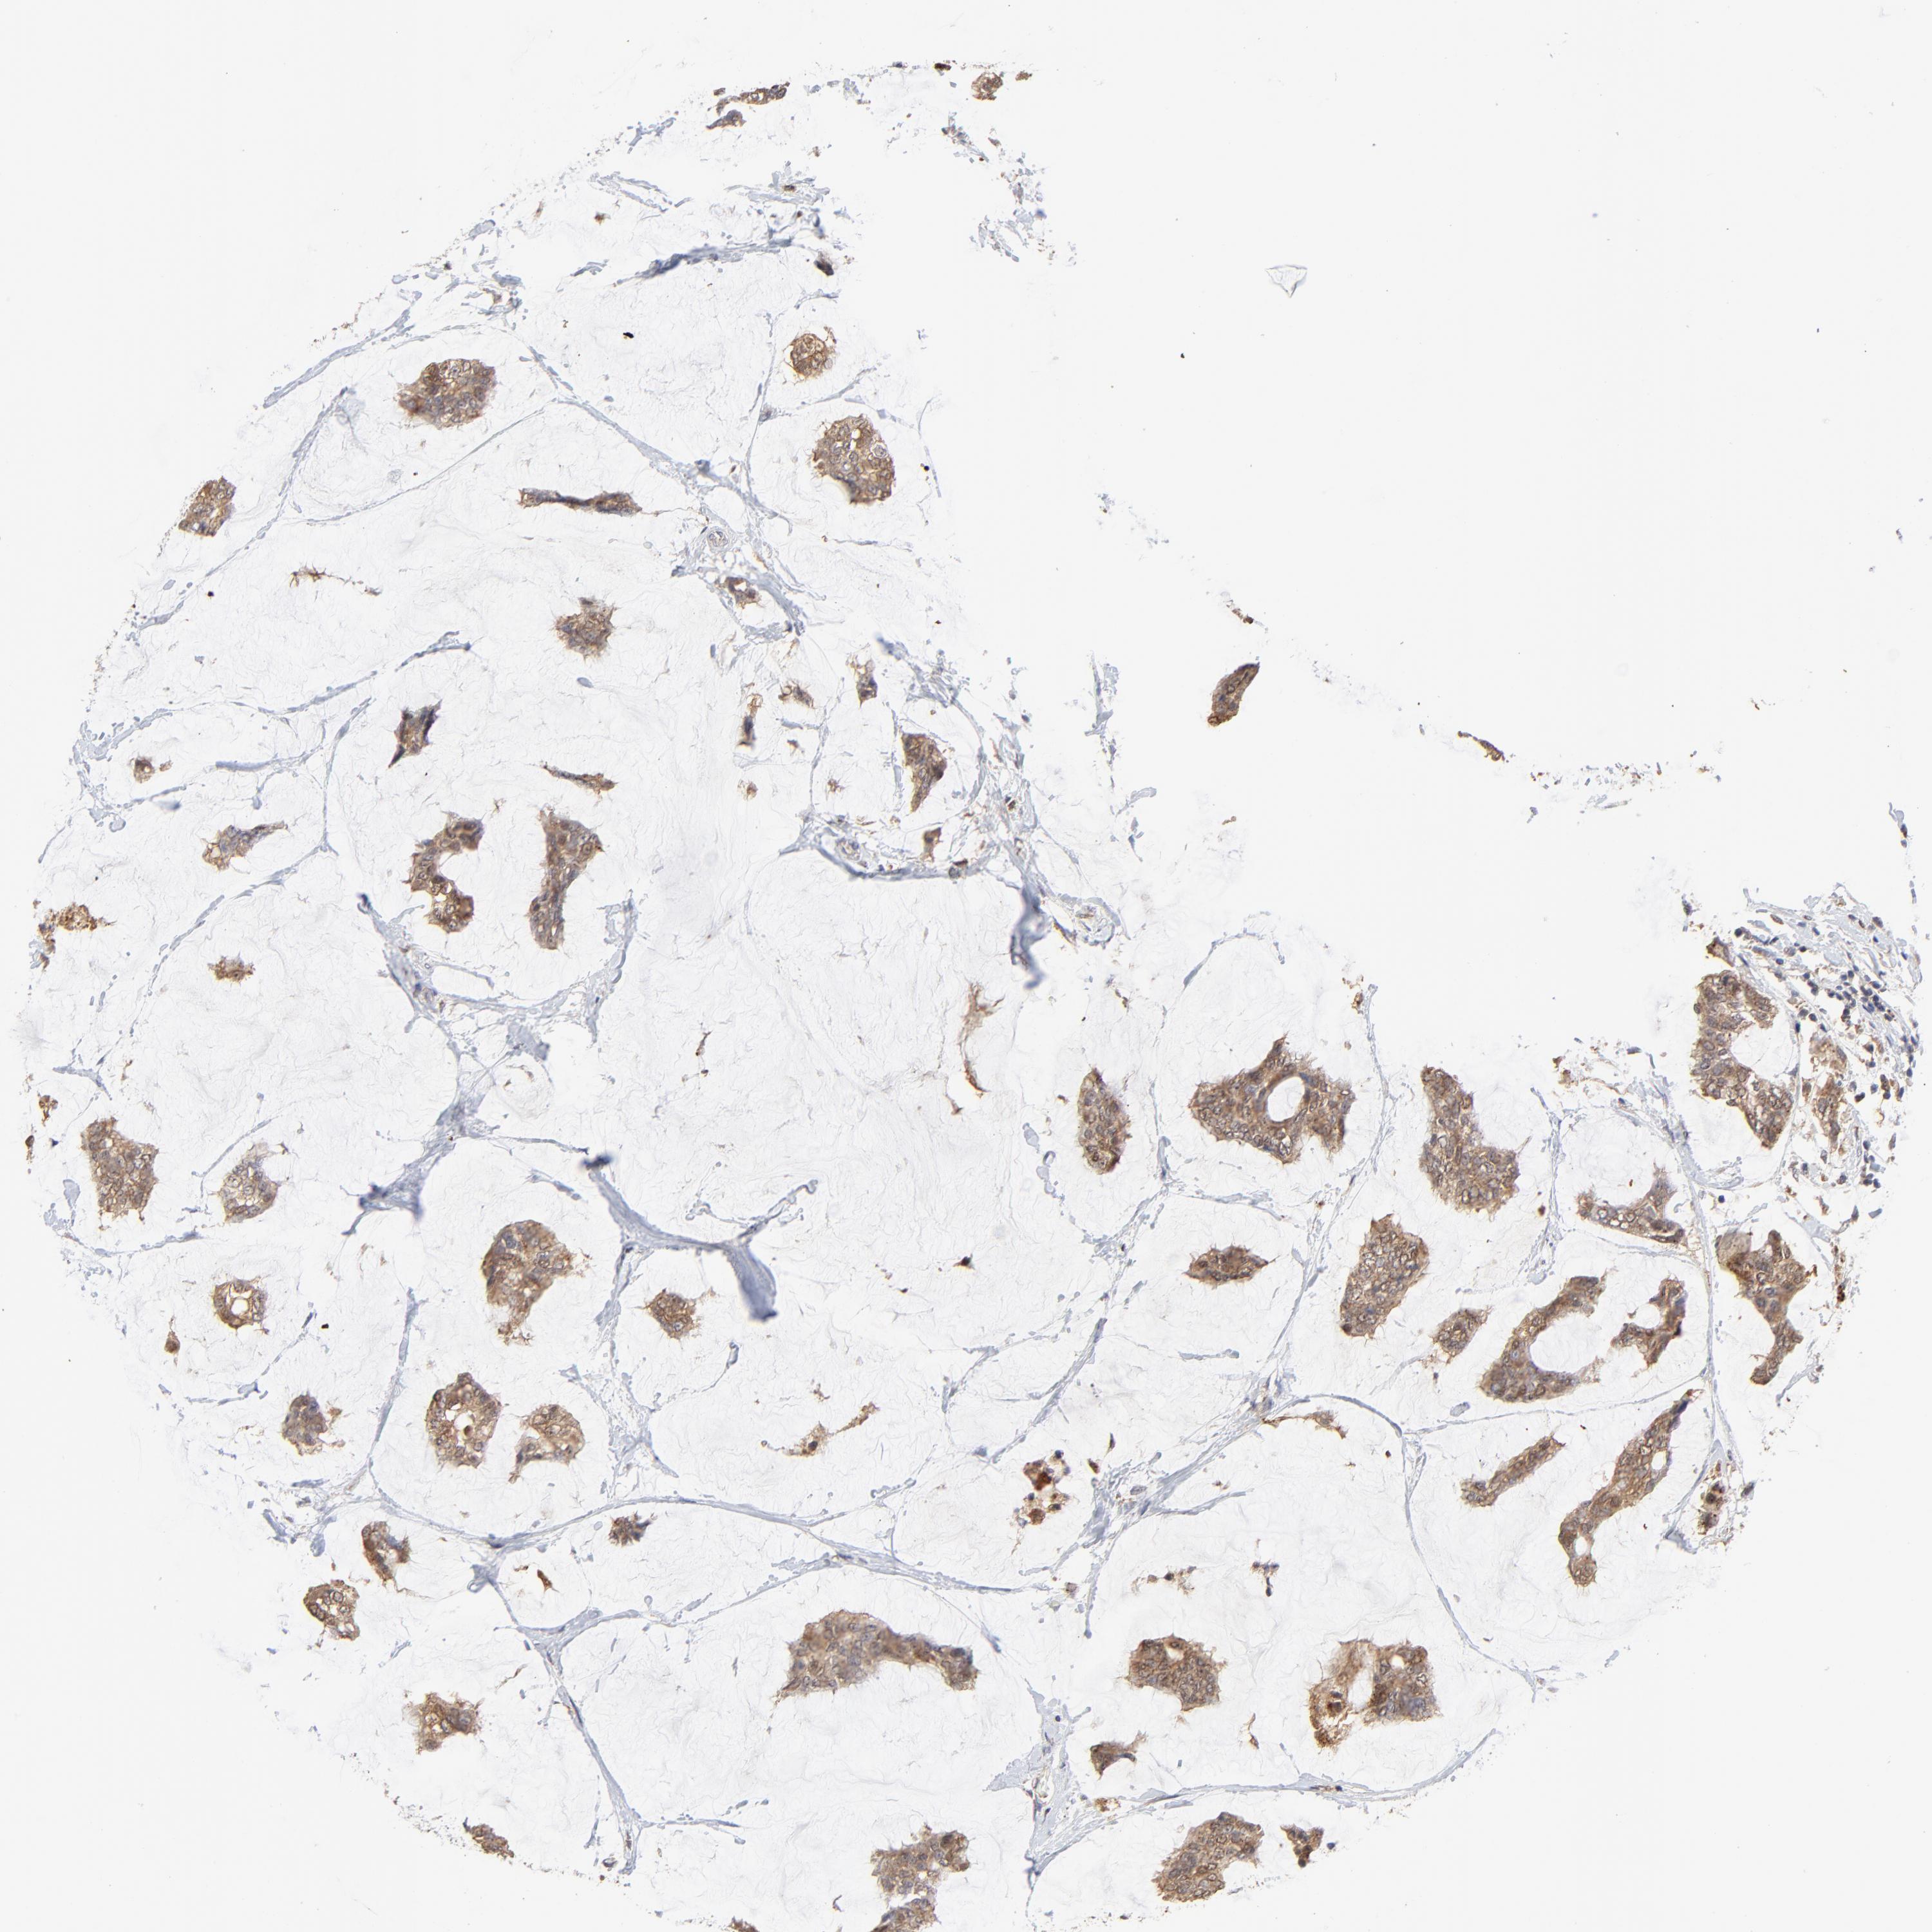

CANCER BREAST CANCER Show tissue menu

BRCA TCGA BRCA VALIDATION PROTEIN EXPRESSION

ANTIBODIES

AND

VALIDATION